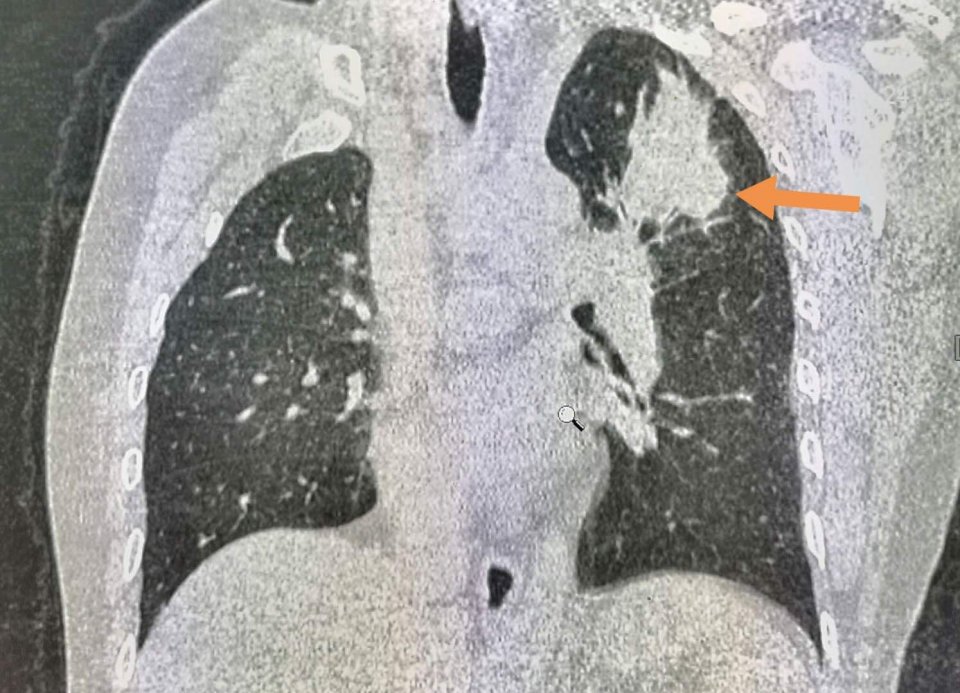

像图中箭头所示这种小肺癌,胸片不显影,肯定会漏诊,但CT可以筛查出来,密切跟踪,及时治愈。

这位女士在钡餐体检时发现左肺尖高密度影。

这里的病灶常见于肺结核、尘肺等,但必须进一步CT检查除外肺癌。

遗憾的是病人没有选择自费进一步检查,自述年轻时可能得过肺结核。

结果一年以后,病灶长大了:

并且发生了淋巴结转移,不能手术了。